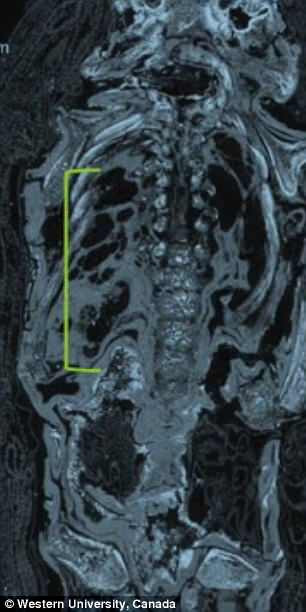

Sự thật chỉ được hé lộ khi Andrew Nelson - nhà khảo cổ sinh vật học và giáo sư ngành nhân chủng học tại Đại học Western Ontario cùng các cộng sự đã thực hiện nghiên cứu xác ướp bằng kỹ thuật chụp cắt lớp vi tính (micro CT scanning) và phát hiện bí mật bất ngờ.

Cụ thể, kết quả kiểm tra cho thấy xác ướp tí hon mà mọi người cứ nghĩ là của diều hâu lại là một đứa trẻ chết yểu khi 23 - 28 tuần tuổi.

Thi hài bé trai này chết non là trường hợp hiếm gặp vì não và hộp sọ cậu bé đã không thể phát triển. Toàn bộ phần đầu hộp sọ đã không được thành hình. Thêm nữa, các đốt sống của cậu bé đã không khít với nhau và tiểu cốt nhĩ lại nằm phía sau đầu.

Theo nhà khảo cổ Nelson, xác ướp bé trai này là một trong 2 xác ướp duy nhất được phát hiện ở Ai Cập mắc phải hội chứng Anencephaly (thiếu một phần não khi sinh).